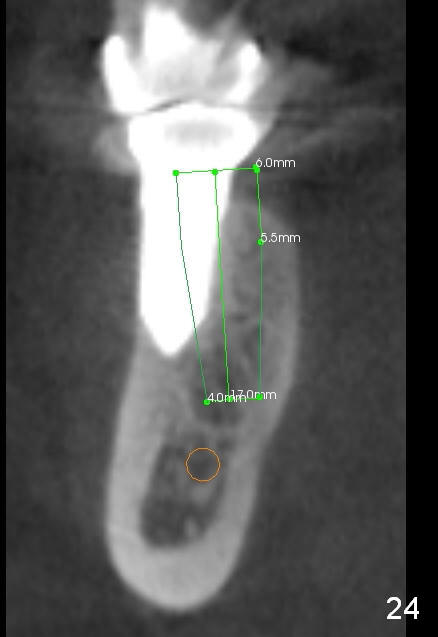

CBCT taken 15 months post cementation shows that the implant is buccally placed (Fig.21 B), associated with possible postop buccal plate resorption (as compared to Fig.23 (coronal section of the site of #19). The buccal plate is not only thinner than the lingual one, but also concave (Fig.22 <). The tooth center (i.e., septum; Fig.23 T) is more buccally located than the center of the basal bone (B). Considering the denser bone lingually, the initial osteotomy should be more lingually (^). If the implant develops infection, it will be replaced by a more lingually placed implant (Fig.24 green).